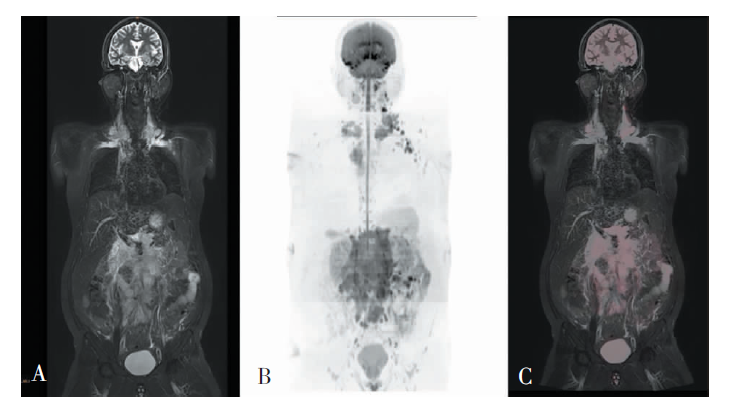

YUE Jingjing, SONG Qi, JIANG Xufeng, WANG Li, ZHAO Weili, YAN Fuhua. Comparison of magnetic resonance whole body diffusion weighted imaging with FS-T2WI and FDG-PET/CT for initial staging and detection of lesion in newly diagnosed lymphoma[J]. Journal of Diagnostics Concepts & Practice, 2021, 20(06): 540-546.